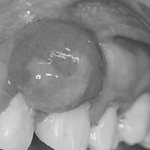

Микроимпланты – это небольшие (диаметром около одного миллиметра) титановые штифты, которые ввинчиваются пациенту в кость, проходят через десну, тем самым являясь надежной опорой для ортодонтической брекет-системы. Они выполняют временную функцию, если ставятся в процессе ортодонтического лечения.

Визуально микроимплант похож на минивинт, при этом имеет специфическую головку. Общая длина микроимпланта составляет от 0,6 до 1,2 см. В отличие от классических имплантов, микроимплант ввинчивается в десну пациента, а при необходимости может быть извлечен без повреждения живых тканей.

Микроимпланты Vector Tas